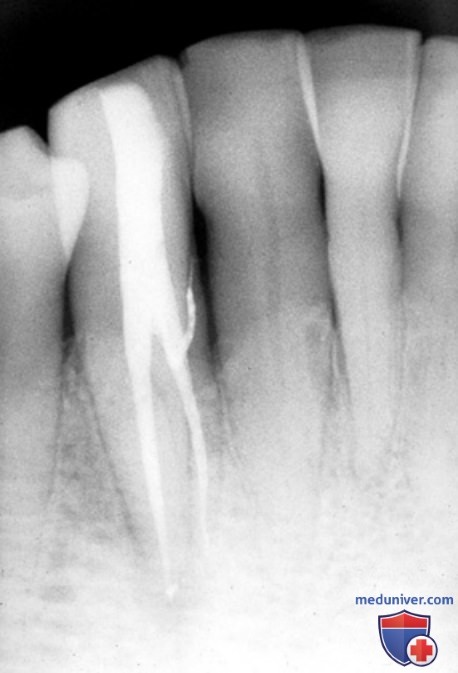

Анатомия: Межкорневая костная перегородка

Раздел: Галерея впечатлений